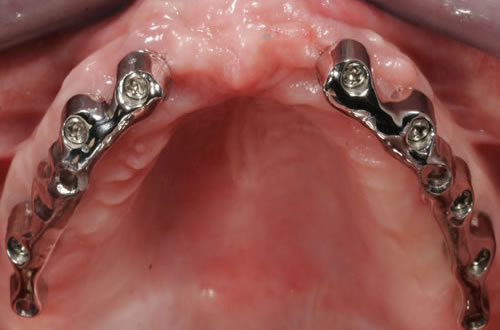

Für den zahnlosen Ober- und Unterkiefer werden dies häufiger Stegkonstruktionen oder Teleskopversorgungen sein (Abb. 8.8 bis 8.16).

Abb. 8.8: Individueller Steg auf 4 Implantaten im zahnlosen Unterkiefer.

Abb. 8.9: Eingesetzter prothesenartiger Zahnersatz.

Abb. 8.10: Individueller Stahlsteg auf 4 Implantaten im zahnlosen Oberkiefer.

Abb. 8.11: Eingegliederter graziler, herausnehmbarer, gaumenfreien Zahnersatz.

Abb. 8.12: Zahnloser Oberkiefer mit 8 Implantaten und eingesetzter Unterkonstruktionen.

Abb. 8.13: Abnehmbare, grazile Brücke.

Abb. 8.14: Zahnloser Oberkiefer mit vier Teleskopen.

Abb. 8.15: Ansicht des Zahnersatzes von unten.

Abb. 8.16: Eingegliederter gaumenfreier Zahnersatz.